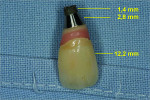

The implant body was fractured into two separate parts. The first portion consisted of the crown, which was still attached to the custom abutment, the smooth neck section, and the first 1.4 mm of the airborne particle–abraded, acid-etched (SLA) surface of the implant (Straumann AG), with a total length of 16.4 mm (Figure 6). The other portion remained in the bone, radiographically measuring 12.6 mm in length (Figure 7). The clinical examination revealed that the fractured portion of the implant body remaining subgingivally was non-movable without bleeding, pain, swelling, or purulent discharge.